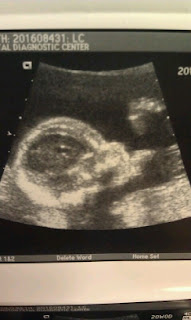

On a not-so-fun note, I spent Sunday evening in Triage again for the

same issues that I was having a few weeks ago. Everything looked awesome with the baby, but the friable cervix is to blame again. :( We have no clue if this will continue throughout the rest of my pregnancy, but they say pregnancy is the culprit as to why it’s happening (it’s nothing that I’m doing like lifting or over exerting myself, which is hard to avoid anyway with a toddler running around). They’ve reassured me this is “normal” in the pregnancy world and everything is going to be just fine so I just have to go with what they tell me and keep on keeping on :) We’re half way there, I’m feeling great, the little dude is starting to let me know he’s in there with his kicks and jabs and we’re counting down the days until we could see his sweet face! I know it may sound crazy to some, but I really like being pregnant. Here’s a look at the bump at 20 weeks 4 days :)